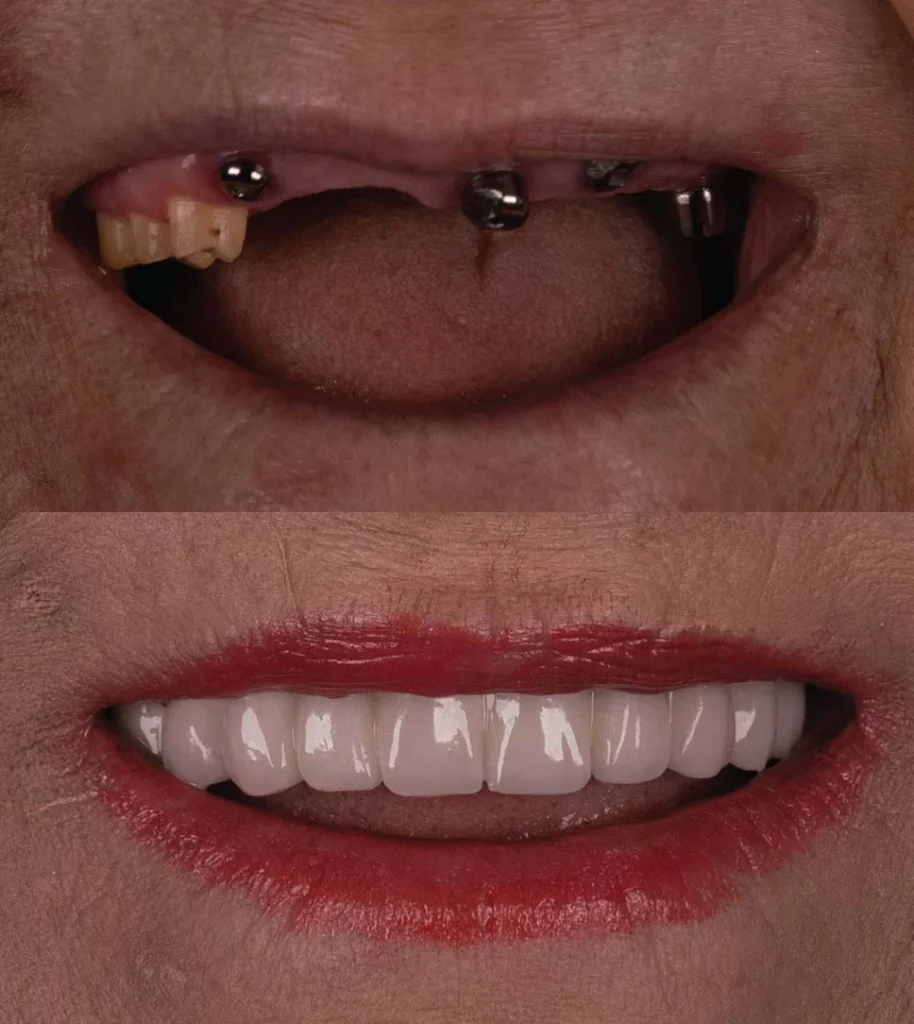

Comprehensive Restoration for Injured Teeth and Oral Structures

Dental trauma can result from accidents, sports injuries, or other incidents that cause damage to your teeth, gums, or jawbone. At Vitalis Dental, we provide comprehensive dental trauma care to restore your oral health and function after such injuries. Our skilled oral surgeons utilize advanced techniques to repair and rehabilitate damaged dental structures.

"After a dental accident, I turned to Vitalis Dental for trauma care. The oral surgeons were incredibly skilled and compassionate, ensuring that my injuries were treated effectively and with care. I'm grateful for their expertise."

The team was compassionate and highly skilled

I suffered a dental injury during a sports event, and Vitalis Dental provided exceptional trauma care. They repaired my chipped tooth beautifully and helped me regain my confidence.

Yes, in many cases, dental trauma care can save and restore your natural tooth. The success depends on the extent of the injury and the promptness of the treatment. Our skilled oral surgeons will assess your condition and provide the best possible care to preserve your tooth.